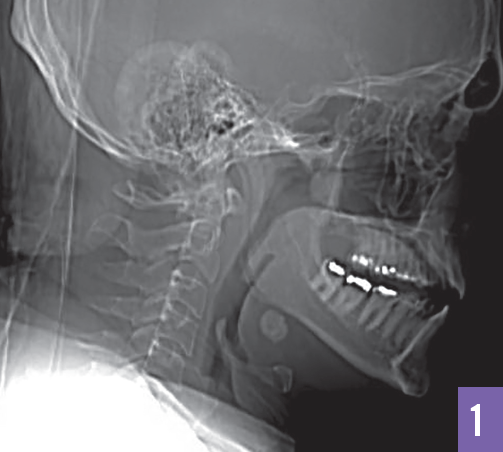

Ricky Kortyna, MMS, PA-C; Emily Murphy, MPAS, PA-C

A 34-year-old man presented with a 2-year history of intermittent painful swelling below the angle of the right mandible.